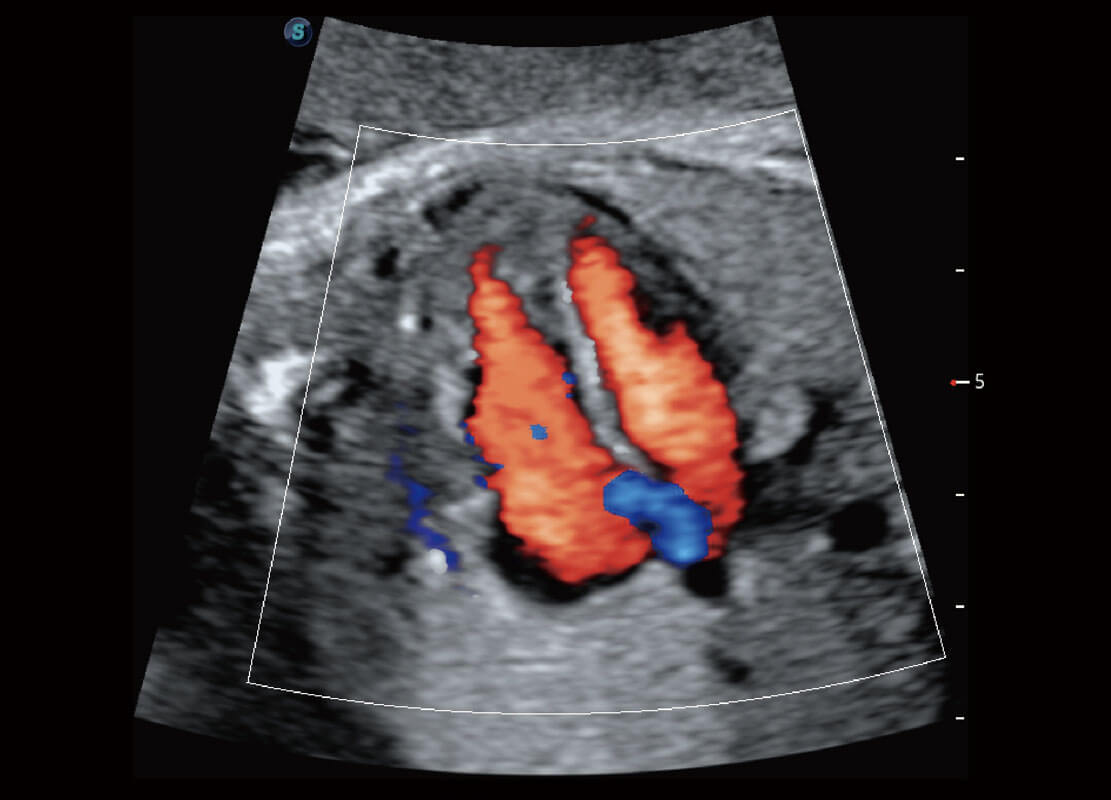

生殖健康

P60优异的图像质量搭载专科探头,在妇科基础疾病的诊断、卵泡生长的监测、输卵管通畅情况的判别等方面为您提供生殖应用方案。

• 腔内妇科-宫腔分离

• 腔内妇科-卵巢